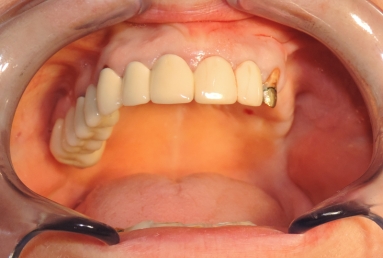

Initial situation: The patient needs dental implants on the left side of the maxillary jaw in order to have a fixed prosthetic restoration. But the bone is insufficient vertically and laterally, because the extractions were made a long time ago, which caused the extreme bone resorption and the vertical migration of the sinus floor.

Final situation: an external sinus lifting procedure was performed. The sinus membrane was lifted off the sinus walls and new bone was applied in the vertical space created ( Bio Oss- switzerland- bovine origin). After 6 months, while the new bone is integrated in the maxillary bone of the patient, dental implants can be applied. the case is still during treatment.